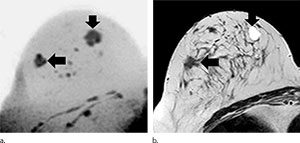

Sebastian Bickelhaupt, M.D., of the German Cancer Research Center, Heidelberg, Germany, and colleagues conducted a prospective institutional review that included 50 women (mean age, 57.1 years; range, 50-69 years), who gave informed consent and who had suspicious screening mammograms and an indication for biopsy from September 2014 to January 2015. Before biopsy, full diagnostic contrast-enhanced MR imaging was performed that included DWIBS (b = 1500 sec/mm2). Two abbreviated protocols (APs) based on maximum intensity projections (MIPs) were evaluated regarding the potential to exclude malignancy: DWIBS (AP1) and subtraction images from the first post-contrast and the unenhanced series (AP2). Diagnostic indexes of both methods were examined using the McNemar test and were compared with those of the full diagnostic protocol and histopathologic findings.

Of the 50 participants, 24 (48 percent) had a breast carcinoma. With AP1 (DWIBS), the sensitivity was 0.92 (95 percent confidence interval [CI]:0.73, 0.98), the specificity was 0.94 (95 percent CI: 0.77, 0.99), the negative predictive value (NPV) was 0.92 (95 percent CI: 0.75, 0.99), and the positive predictive value (PPV) was 0.93 (95 percent CI: 0.75, 0.99). The mean reading time was 29.7 seconds (range, 4.9–110.0 seconds) and was less than 3 seconds (range, 1.2–7.6 seconds) in the absence of suspicious findings on the DWIBS MIPs. With the AP2 protocol, the sensitivity was 0.85 (95 percent CI: 0.78, 0.95), the specificity was 0.90 (95 percent CI: 0.72, 0.97), the NPV was 0.87 (95 percent CI: 0.69, 0.95), the PPV was 0.89 (95 percent CI: 0.69, 0.97), and the mean reading time was 29.6 seconds (range, 6.0–100.0 seconds).

Unenhanced diagnostic MR imaging–DWIBS mammography achieved a comparable accuracy to the full diagnostic protocol and to abbreviated contrast-enhanced protocols when used as a complementary method after screening mammography, according to researchers.

“The comprehensive method is fast and robust to perform as a complement to routine mammography. Along with lack of need for intravenous contrast agent administration, ad-vantages include its short acquisition time of less than seven minutes and short reading time of less than 30 seconds,” the authors write.